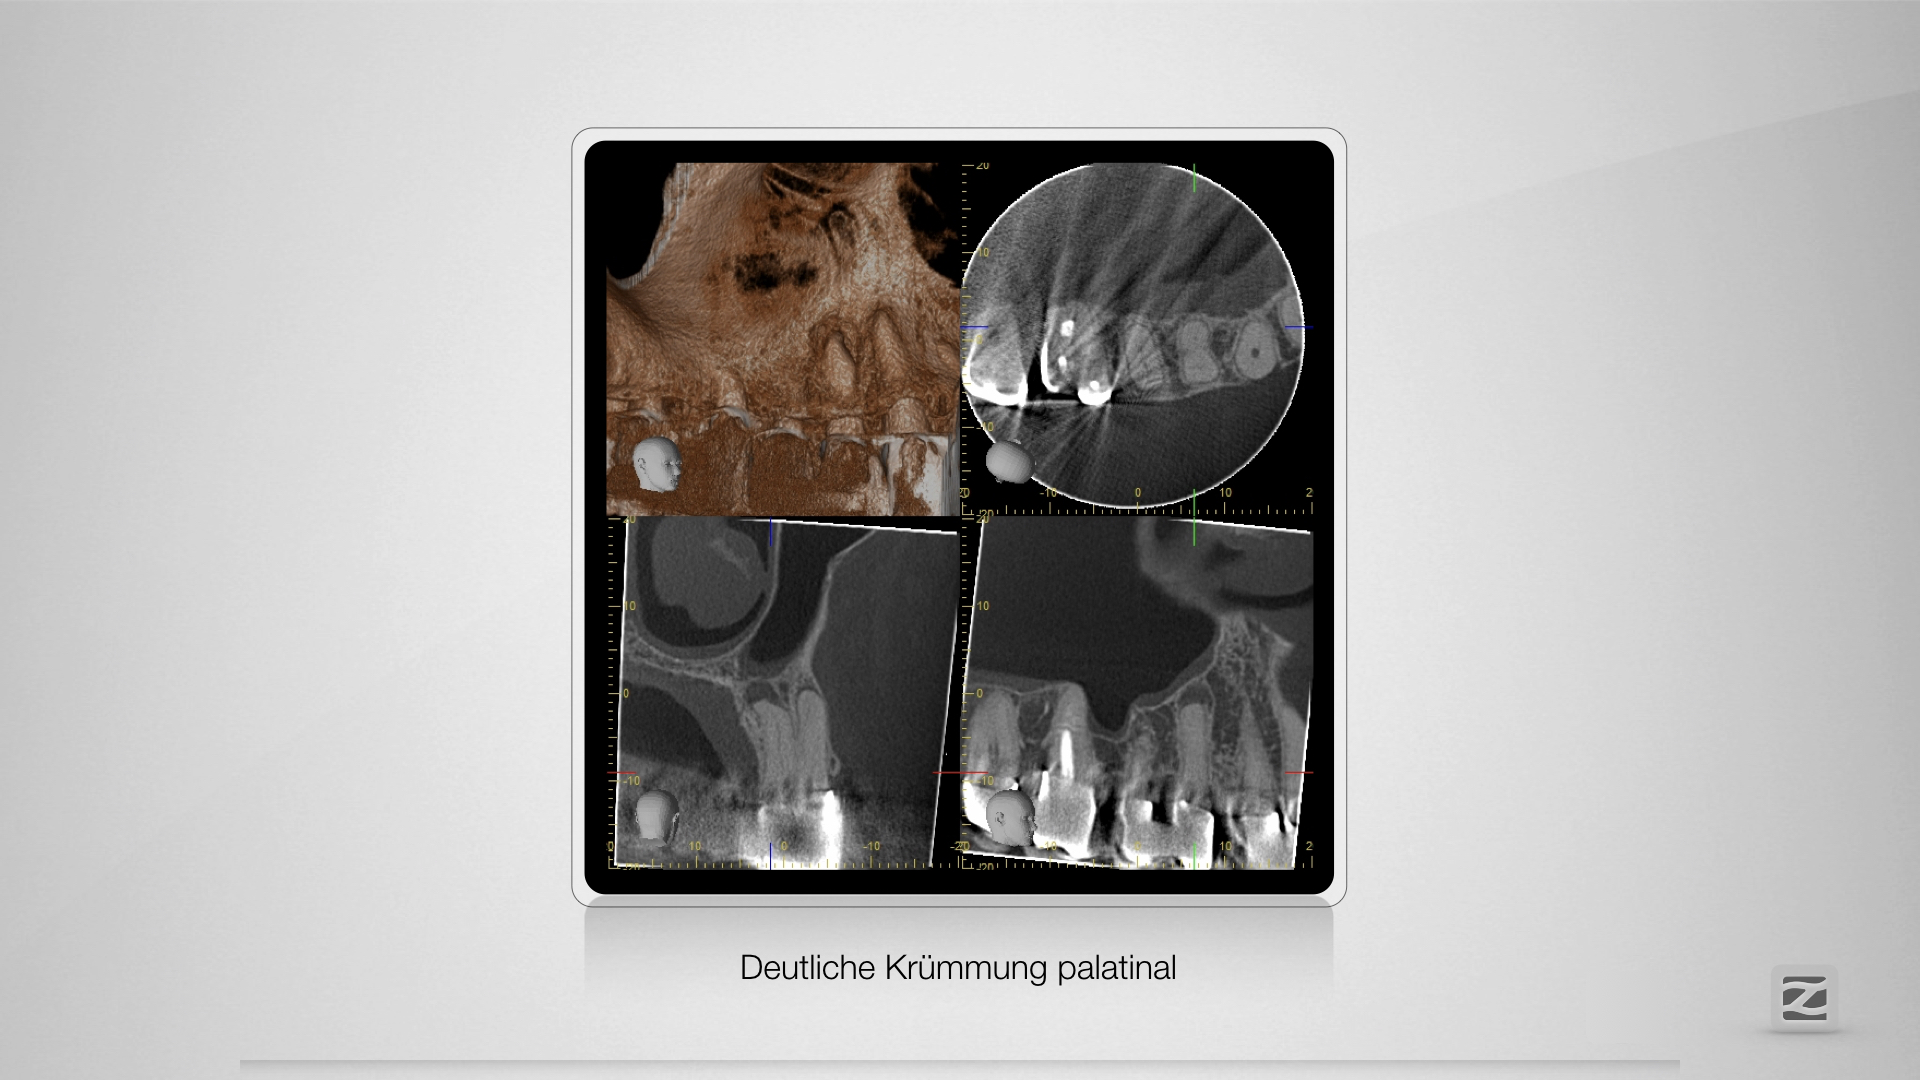

Dummheit gehört bestraft.